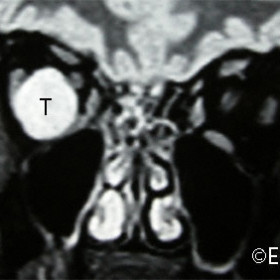

Choroidal Melanoma

Choroidal Melanoma - MRI CORONAL section demonstrates massive extrascleral tumor extension (T).